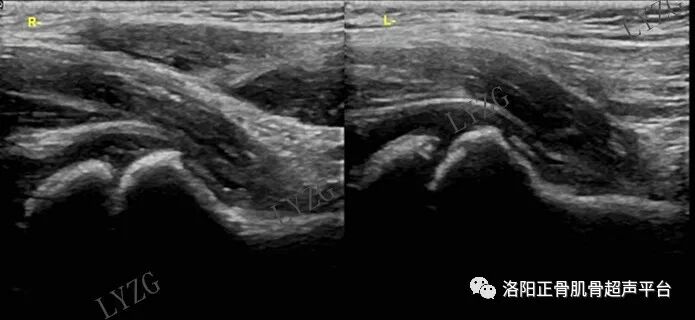

小儿正常髋关节超声表现

双侧髋关节前隐窝内均可见小于2mm的滑液

双侧髋关节前隐窝内均可见细带状滑液